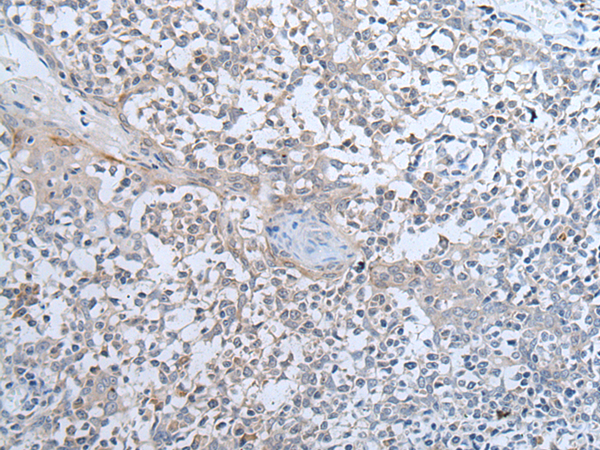

分类: 科研抗体货号: P12753别名: 9-27; CD225; IFI17; LEU13; DSPA2a应用: WB,IHC反应种属: Human, Mouse